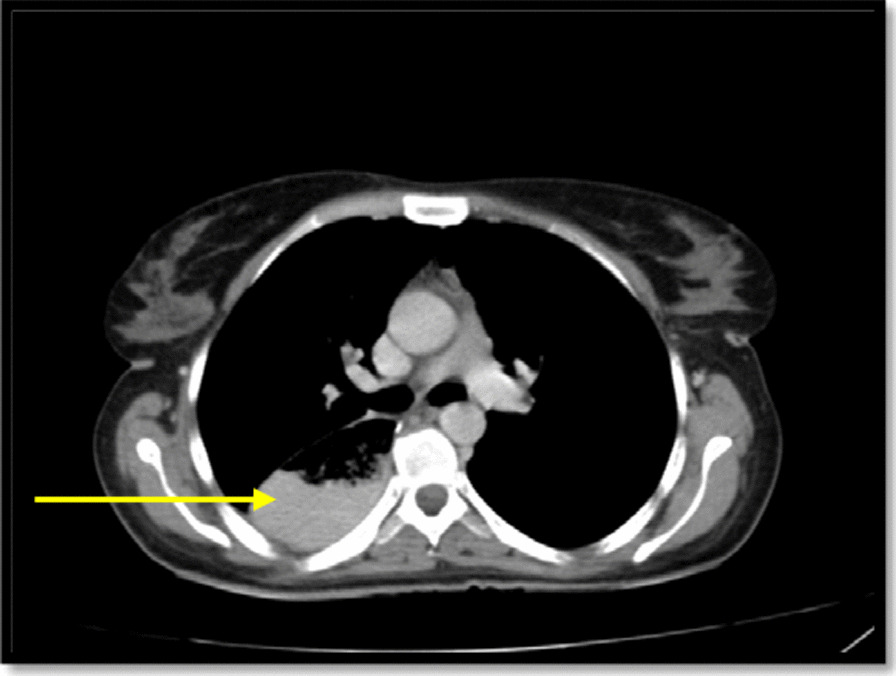

Afterward a multidisciplinary team decision-making meeting (weekly general surgery grand round at the department of surgery, Shahid Beheshti Hospital, Yasuj University of Medical Sciences) was held, and it was decided that the patient would receive 3 sessions of chemotherapy without radiotherapy before undergoing the operation. Then, the patient underwent three field esophagectomy (McKeown) including laparotomy, right thoracotomy, and gastric pull-up with cervical anastomosis including extended thoracotomy, esophagectomy, gastric pull-up, pyloroplasty, cervical esophagostomy, jejunostomy, and chest tube insertion. An abdominal LN at the gastrohepatic ligament was also resected. The postoperative course was uncomplicated. There was no evidence of the leak at the anastomotic site by administration of methylene blue dye on the fifth postoperative day and then nasogastric tube was removed and the patient was told to start drinking liquids. The patient advanced to a regular diet by the tenth postoperative day. She was discharged from the hospital on the 14th day of admission. At a follow-up visit of 1 week and then 2 weeks after discharge from the hospital she was feeling well. The patient’s condition after surgery came back to her normal habitual life within 3 months. The patient had no complaint at the 9th month follow-up visit after surgery. A spiral chest and abdomen CT scan was done and showed a pulled-up stomach, filled with fluid and air at the right paraspinal region (Fig. 4). In the last follow-up, the patient had no complaints and said that she ate a satisfying meal recently, and that she is optimist about the future.

Fig. 4.

Spiral chest CT scan: pulled-up stomach at the right paraspinal region shown with a yellow arrow